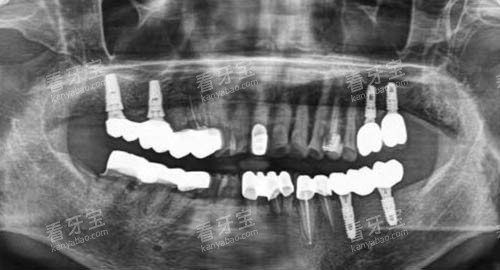

在种植牙领域,AI智能化导航种植技术能够精密定位种植体的位置和深度,降低手术风险,提高种植成功几率,减少患者的痛苦和修复时间。